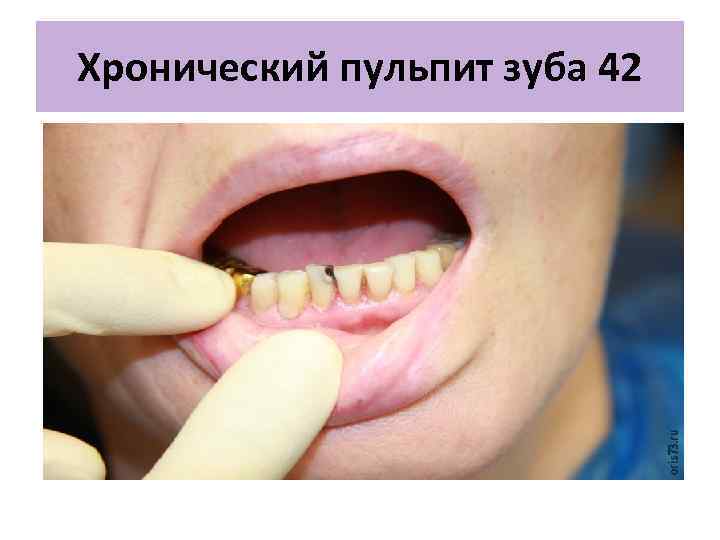

Хронический пульпит зуба 42